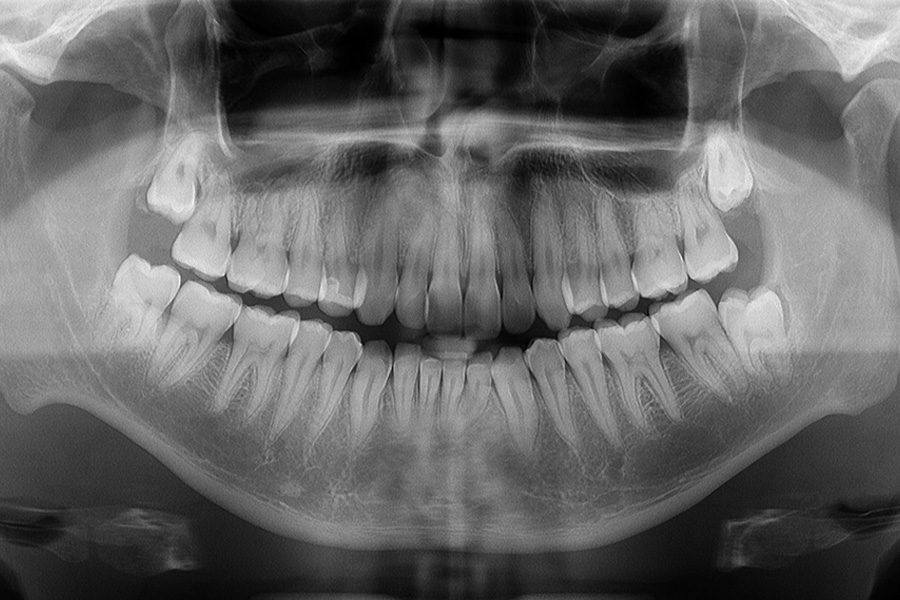

抜髄が必要になる歯では、大きなむし歯が原因となっていることが少なくありません。

そのむし歯を取り除くと、歯の一部が大きく欠損してしまうことがあります。

特に歯の上部(歯髄腔周辺)や根管の入り口(根管口)で石灰化が起こると、神経の部屋や根管の位置を見つけることが困難になります。

エックス線画像やCBCT画像によって根管の形態を事前に把握し、マイクロスコープを用いて治療を行うことで、石灰化した根管にも適切に対応することができます。